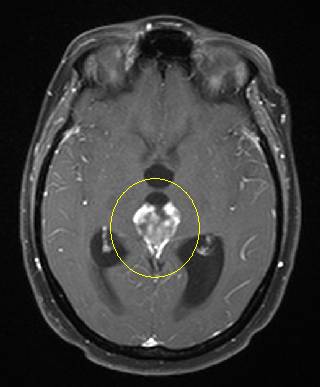

another picture with a small enhancing lesion with

massive edema...was NOT a brain met but

an infection with toxoplasmosis